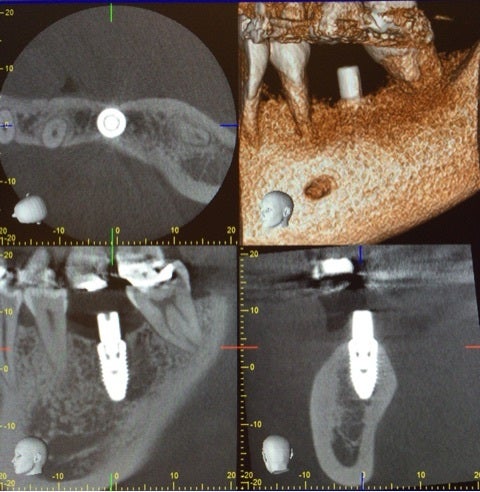

それでは当院でのインプラント手術の例です。

患者様は左下の奥歯が欠損してしまい、しっかり食事を摂りたいという希望で無痛治療でのインプラント手術を選択されました。

術前に綿密にシミュレーションを行っていたものとほぼ同じ位置に埋入されていることが確認できます。

今回は埋入手術の話ですが、当院では上記にお話ししたインプラントの成立要件を全て確認し、シミュレーションを行い手術を行っています。